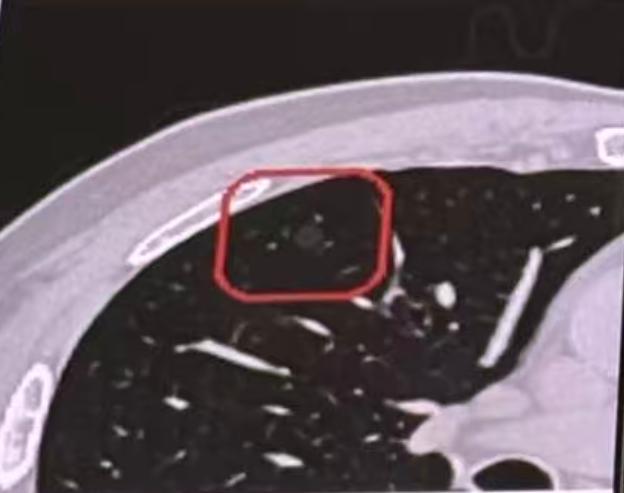

肺结节确实发现得越来越多了,很多朋友在发现肺结节后,会感到特别紧张,但我认为,大家应当放下心理包袱,该观察时就安心观察! 尤其是对于直径小于一公分的肺小结节,或者含有磨玻璃成分的肺结节,即便是肿瘤性质,其发展也往往非常缓慢,通常不会对身体健康和生命安全构成直接威胁。 因此,选择观察是最好的策略——以不变应万变,在确保身体安全的前提下,避免因过度医疗干预带来不必要的损伤。观察,本身就是一种稳妥的处理措施。 当然,如果在观察期间发现结节出现变化,比如大小增大或密度增加,就提示结节可能具有一定危险性,可能对健康乃至生命造成影响。此时,就需要及时、果断地进行干预处理。 但临床上也会遇到一些特殊情况:比如结节虽然出现了变化,但患者同时发现心脏问题,或家庭突发急事,暂时无法接受手术。在这种情况下,是否可以缓一缓、短期再观察一下呢? 其实,像磨玻璃结节这类惰性结节,发展进程非常缓慢,即使已发现变化,若因特殊原因短期内无法处理,再适当短期观察一般也是允许的。[玫瑰][作揖]